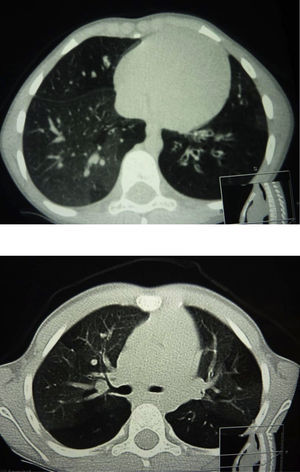

La TCAR pulmonar objetivó patrón en mosaico en 22 casos (100%) y bronquiectasias en 8 (36,36%) (fig. 1). Se realizó gammagrafía pulmonar ventilación perfusión y biopsia pulmonar en 1 caso (4,54%) por dudas diagnósticas, confirmándose el diagnóstico de bronquiolitis obliterante.

Anteriormente se ha considerado la biopsia pulmonar como patrón oro para el diagnóstico de BO en población no trasplantada1. Sin embargo, actualmente la TCAR está sustituyendo a la biopsia pulmonar como técnica para el diagnóstico precoz de esta entidad25. Resultan características las áreas de patrón en mosaico, las áreas de atrapamiento aéreo con distribución irregular, la atenuación vascular, las bronquiectasias, la obliteración de la luz bronquial y la hipoatenuación del parénquima pulmonar. Además, la biopsia puede no ser diagnóstica en esta enfermedad con patrón de distribución heterogéneo y puede ser normal o no concluyente hasta en un tercio de los pacientes24,26. Otras técnicas como la gammagrafía pulmonar de ventilación y perfusión que característicamente muestra un patrón en parches moderado o severo de defectos en la ventilación y la perfusión del parénquima pulmonar está siendo actualmente sustituida por el TCAR pulmonar2. En nuestra cohorte, se ha realizado el diagnóstico de BO en base a la historia clínica compatible, la TCAR pulmonar y las pruebas de función pulmonar. Solamente en un caso con dudas diagnósticas fue necesario realizar biopsia pulmonar. Se ha descrito que el engrosamiento de la pared bronquial y el patrón en mosaico son las características con mayor especificidad (≥99%) y las bronquiectasias las de mayor sensibilidad (80%)25,27. En nuestra muestra, la TCAR objetivó patrón en mosaico en 22 casos (100%) y bronquiectasias en 8 (36,36%). La realización del TCAR pulmonar en inspiración y en espiración incrementa la capacidad para detectar atrapamiento aéreo y patrón en mosaico. En pacientes de corta edad no colaboradores, la posición en decúbito lateral resulta útil para identificar atrapamiento aéreo cuando existe un patrón de atenuación pulmonar en mosaico28.